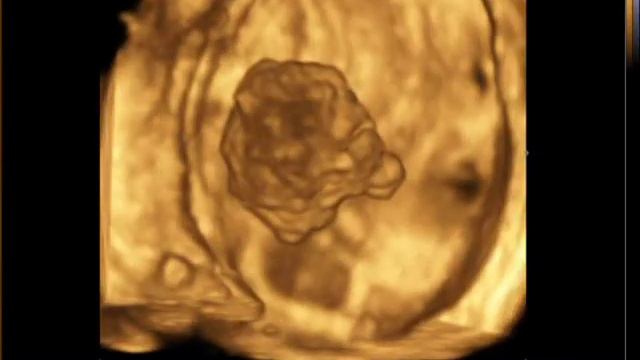

Опухоль мочевого пузыря